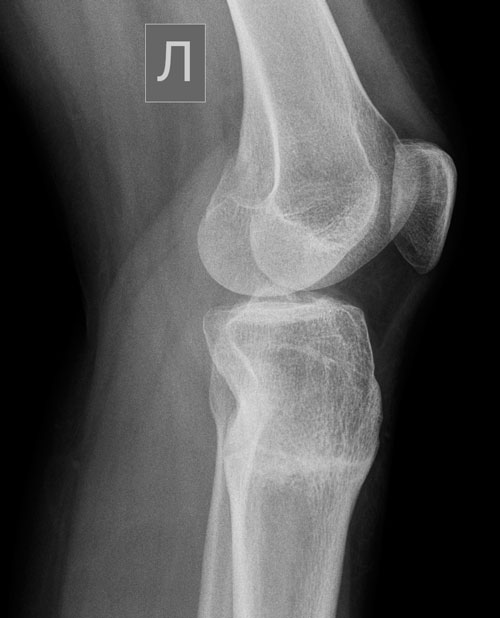

Здравствуйте, дорогой Николай Николаевич и милая Наталья. Уже почти 2 месяца со снятия и мне даже не вериться, что у меня когда-то была операция, а тем более что у меня были кривые ноги. Чувствую себя отлично, ноги не беспокоят, только радуют. Походы по магазинам теперь праздник, а не сплошное расстройство как раньше. Николай Николаевич! Всей моей благодарности к Вам просто не выразить словами. За каждый день моей новой счастливой жизни буду благодарна Вам!!! Вы не просто хирург с золотыми руками, но и ЧЕЛОВЕК с золотым сердцем.

Кстати, измерила на днях свой рост +2 см, приятный сюрприз!!!

Почти 2 месяца с момента снятия аппаратов.